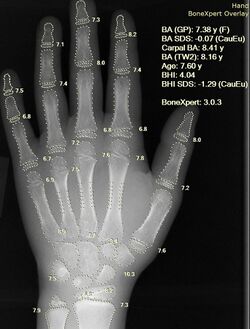

Imaging

Determination of bone age allows for comparison with chronological age and assessment of future growth potential.

Since bone maturation is a good indicator of overall physical maturation, an x-ray of the left hand and wrist to assess bone age usually reveals whether the child has reached a stage of physical maturation at which puberty should be occurring.[2][7] X-ray displaying a bone age <11 years in girls or <13 years in boys (despite a higher chronological age) is most often consistent with constitutional delay of puberty.[7][37] An MRI of the brain should be considered if neurological symptoms are present in addition to delayed puberty, two findings suspicious for pituitary or hypothalamic tumors.[2][10] An MRI can also confirm the diagnosis of Kallmann syndrome due to the absence or abnormal development of the olfactory tract.[10] However, in the absence of clear neurological symptoms, an MRI may not be the most cost-effective option.[10] A pelvic ultrasound can detect anatomical abnormalities including undescended testes and müllerian agenesis.[2][36]